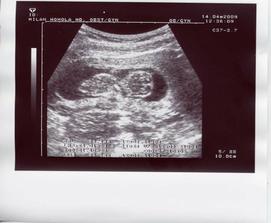

14.4. Druhá KO - tlak OK, krevní testy taky až na snížený hemoglobin (dostala jsem prášky), UTZ - mimísek už má 54,1 mm a odpovídá 12+0 tt, dle MS 11+3 tt, vše je naprosto OK! Termín předběžně posunut na 27.10.2009. Mimísek sebou pěkně mrskal, doktor ho nemohl vůbec změřit natož vyfotit ;o). Mával ručičkama a kopal nožičkama a kroutil se do všech stran. Příští kontrola zase za 3 týdny, snad semnou půjde i manža.